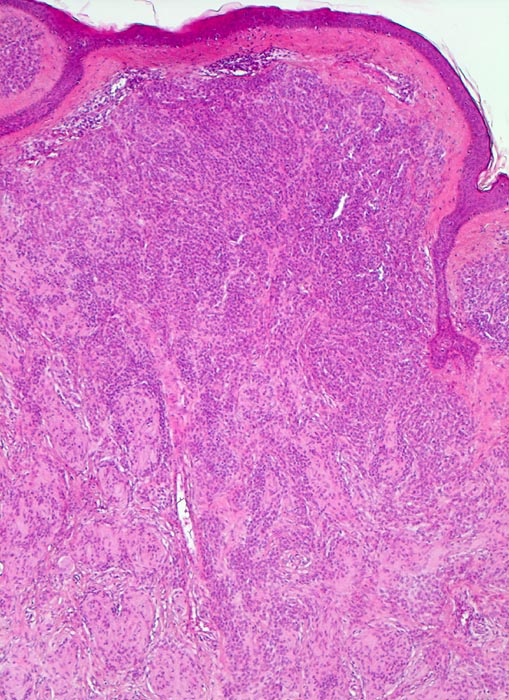

• Symmetrischer leicht exophytischer Tumor.

• Die Tumorzellen bilden Nester in der Epidermis und in der Dermis (=dermoepidermaler bzw. compound Naevus).

• Die oberflächlichen Naevuszellen zeigen reichlich helles, teils pigmentiertes Zytoplasma und helle ovale Kerne mit kleinen, deutlich erkennbaren Nukleolen. Zur Tiefe hin werden die Naevuszellen kleiner, haben weniger Zytoplasma und dunkle kleine Kerne ohne gut erkennbaren Nucleolus. Die Zellnester werden zur Tiefe hin ebenfalls kleiner (=Ausreifung).

Kennzeichnend für einen gutartigen Naevuszellnaevus ist dessen Symmetrie und die Ausreifung der intradermalen Naevuszellen von oberflächlich gelegenen grossen, runden, pigmentierten Zellen in grossen Nestern, zu tiefer gelegenen kleineren, runden, nicht pigmentierten, in kleineren Nestern oder einzeln liegenden Zellen und in älteren Läsionen zu spindeligen Zellen mit neuralem Phänotyp mit Verlust der melanozytären Differenzierung (sogenannter Neuronaevus). Gewöhnliche Naevi zeigen keine zytologischen Atypien und die dermale mitotische Aktivität ist minimal. Es existieren verschiedene Varianten erworbener Naevi, welche klinisch und/oder histologisch Melanome imitieren können. Zu diesen Varianten gehören Halo Naevi, kombinierte Naevi, Spitz Naevi, blaue Naevi und dysplastische Naevi.

Erworbene Naevi können ein lentiginöses oder ein kongenitales Wachstumsmuster aufweisen (Ausbreitung der Naevuszellen in der tieferen Dermis entlang von Adnexstrukturen). Letzteres bedeutet nicht, dass der Naevus bei Geburt schon bestand. Am Anfang der Entwicklung erworbener Naevi steht die Lentigo simplex (> 5299), welche durch Vermehrung einzeln liegender Melanozyten im Bereich der basalen Epidermis zustande kommt und makroskopisch als scharf begrenzte braune Makula imponiert. Daraus entwickeln sich junktionale Naevi mit Nestern von jeweils drei oder mehr Naevuszellen in der basalen Epidermis (> 5362). Bei Compound Naevi (= dermoepidermaler Naevuszellnaevus) finden sich zusätzlich zu den epidermalen auch intradermal gelegene Naevuszellen oder Nester von Naevuszellen (> 565). Compound Naevi zeigen ein sehr variables makroskopisches Bild von gering erhabenen bis zu polypoiden, gestielten oder verrukösen Läsionen. Die Farbe variiert von braun über grau bis zu hautfarben. Diese Naevi bleiben über Jahre weitgehend unverändert und entwickeln sich schliesslich weiter zu rein dermalen (=corialen) Naevi mit ausschliesslich intradermal gelegenen, oftmals unpigmenierten Naevuszellen, um schliesslich vollständig zu verschwinden.